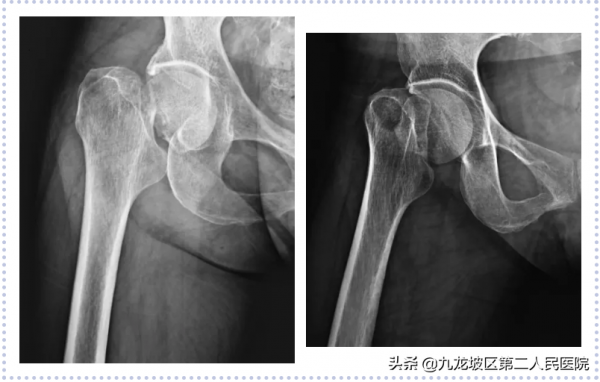

74歲女性,因“高處跌落致右髖部疼痛伴活動受限2+小時”入院。診斷為“右股骨頸骨折(GardenⅣ型)”。2021年04月26日在我院骨科行右全髖關節置換術。術後第5天扶助行器下地行走。